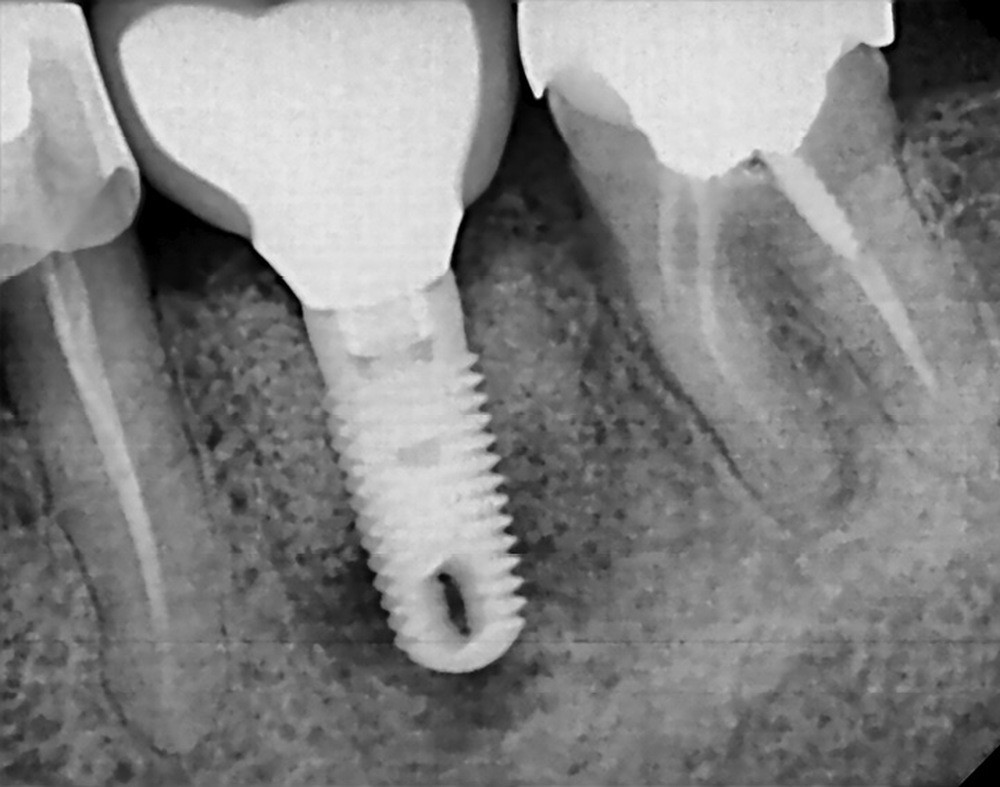

La préservation de l’ostéointégration dépend de la santé des tissus péri-implantaires mais aussi du contrôle des forces occlusales (fig. 1) [2].

D’après la récente classification de Chicago (2017) des maladies parodontales et péri-implantaires, la péri-implantite est définie comme une pathologie induite par un biofilm dysbiotique, et caractérisée par une inflammation de la muqueuse péri-implantaire et par une perte progressive du support osseux. C’est donc un processus inflammatoire le plus souvent lent et irréversible qui atteint les tissus mous et durs péri-implantaires [3]. L’étude menée par Mombelli et coll. en 2012 montre que 20 % des patients chez qui il a été posé des implants et 10 % des implants posés déclareront une péri-implantite dans les cinq à dix ans après la pose (fig. 2) [4].